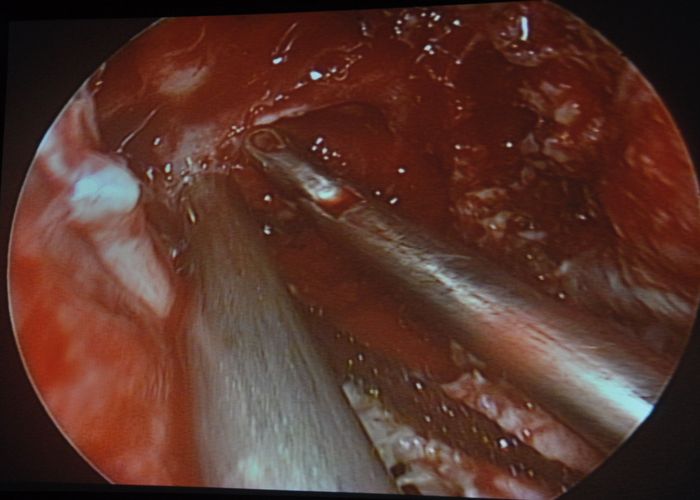

दूसरी सर्जरी बीरबल की हुई जो स्लिप डिस्क से परेशान था। उसकी एल-4 और एल-5 डिस्क में अतिवृद्धि के कारण तंत्रिका पर दबाव पड़ रहा था। बीरबल की पीछ के पीछे 1.8 सेंटीमीटर का छेदकर उसमें एण्डोस्कोप डाला गया और अतिवृद्धि को काटकर तंत्रिका को सुचारू कर दिया गया।

वर्तमान में स्लिप डिस्क सर्जरी में पीठ पर चीरा लगाकर की जाती है। सर्जरी में अस्पताल के न्यूरो सर्जन विभागाध्यक्ष व अस्पताल अधीक्षक डॉ. सुनील गर्ग और डॉ. शरद थानवी ने भी भाग लिया।